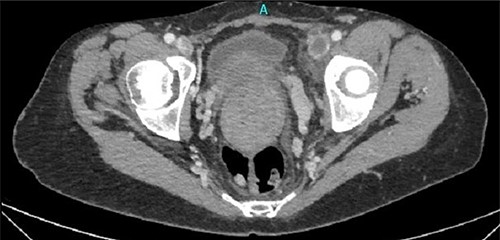

Under fluoroscopy, an aortic occlusion balloon catheter (Reliant AB46 Medtronic Minneapolis, SENSH 1228 W) through a 12F introducer sheath was inserted to the right internal jugular vein into the IVC and was positioned in the restricted free inferior caval space just below the renal veins (Fig. 3). Before the final placement of the balloon and the initiation of any surgical procedure, the hemodynamic condition of the patient was checked during the placement and extension of the balloon. No hemodynamic instability was observed, so the operation proceeded to the next step. The catheter balloon was inflated with the appropriate volume of physiologic saline solution to occlude the IVC and the operation began. The temporal vena cava occlusion continued until the fibroid mobilization and the proximal control of the thrombosed left common iliac vein. After mass mobilization, the vena cava was checked manually for possible clots within the vein, coming from the common iliac veins, especially from the left one. Following removal of the fibroids with the uterus, the occlusion balloon was deflated and removed without any complication. The blood pressure and heart rate were monitored continuously throughout the operation; no significant changes occurred. A total hysterectomy with bilateral adnexectomy was also conducted.

Under fluoroscopy, an aortic occlusion balloon catheter was positioned in the restricted free inferior caval space just below the renal veins.